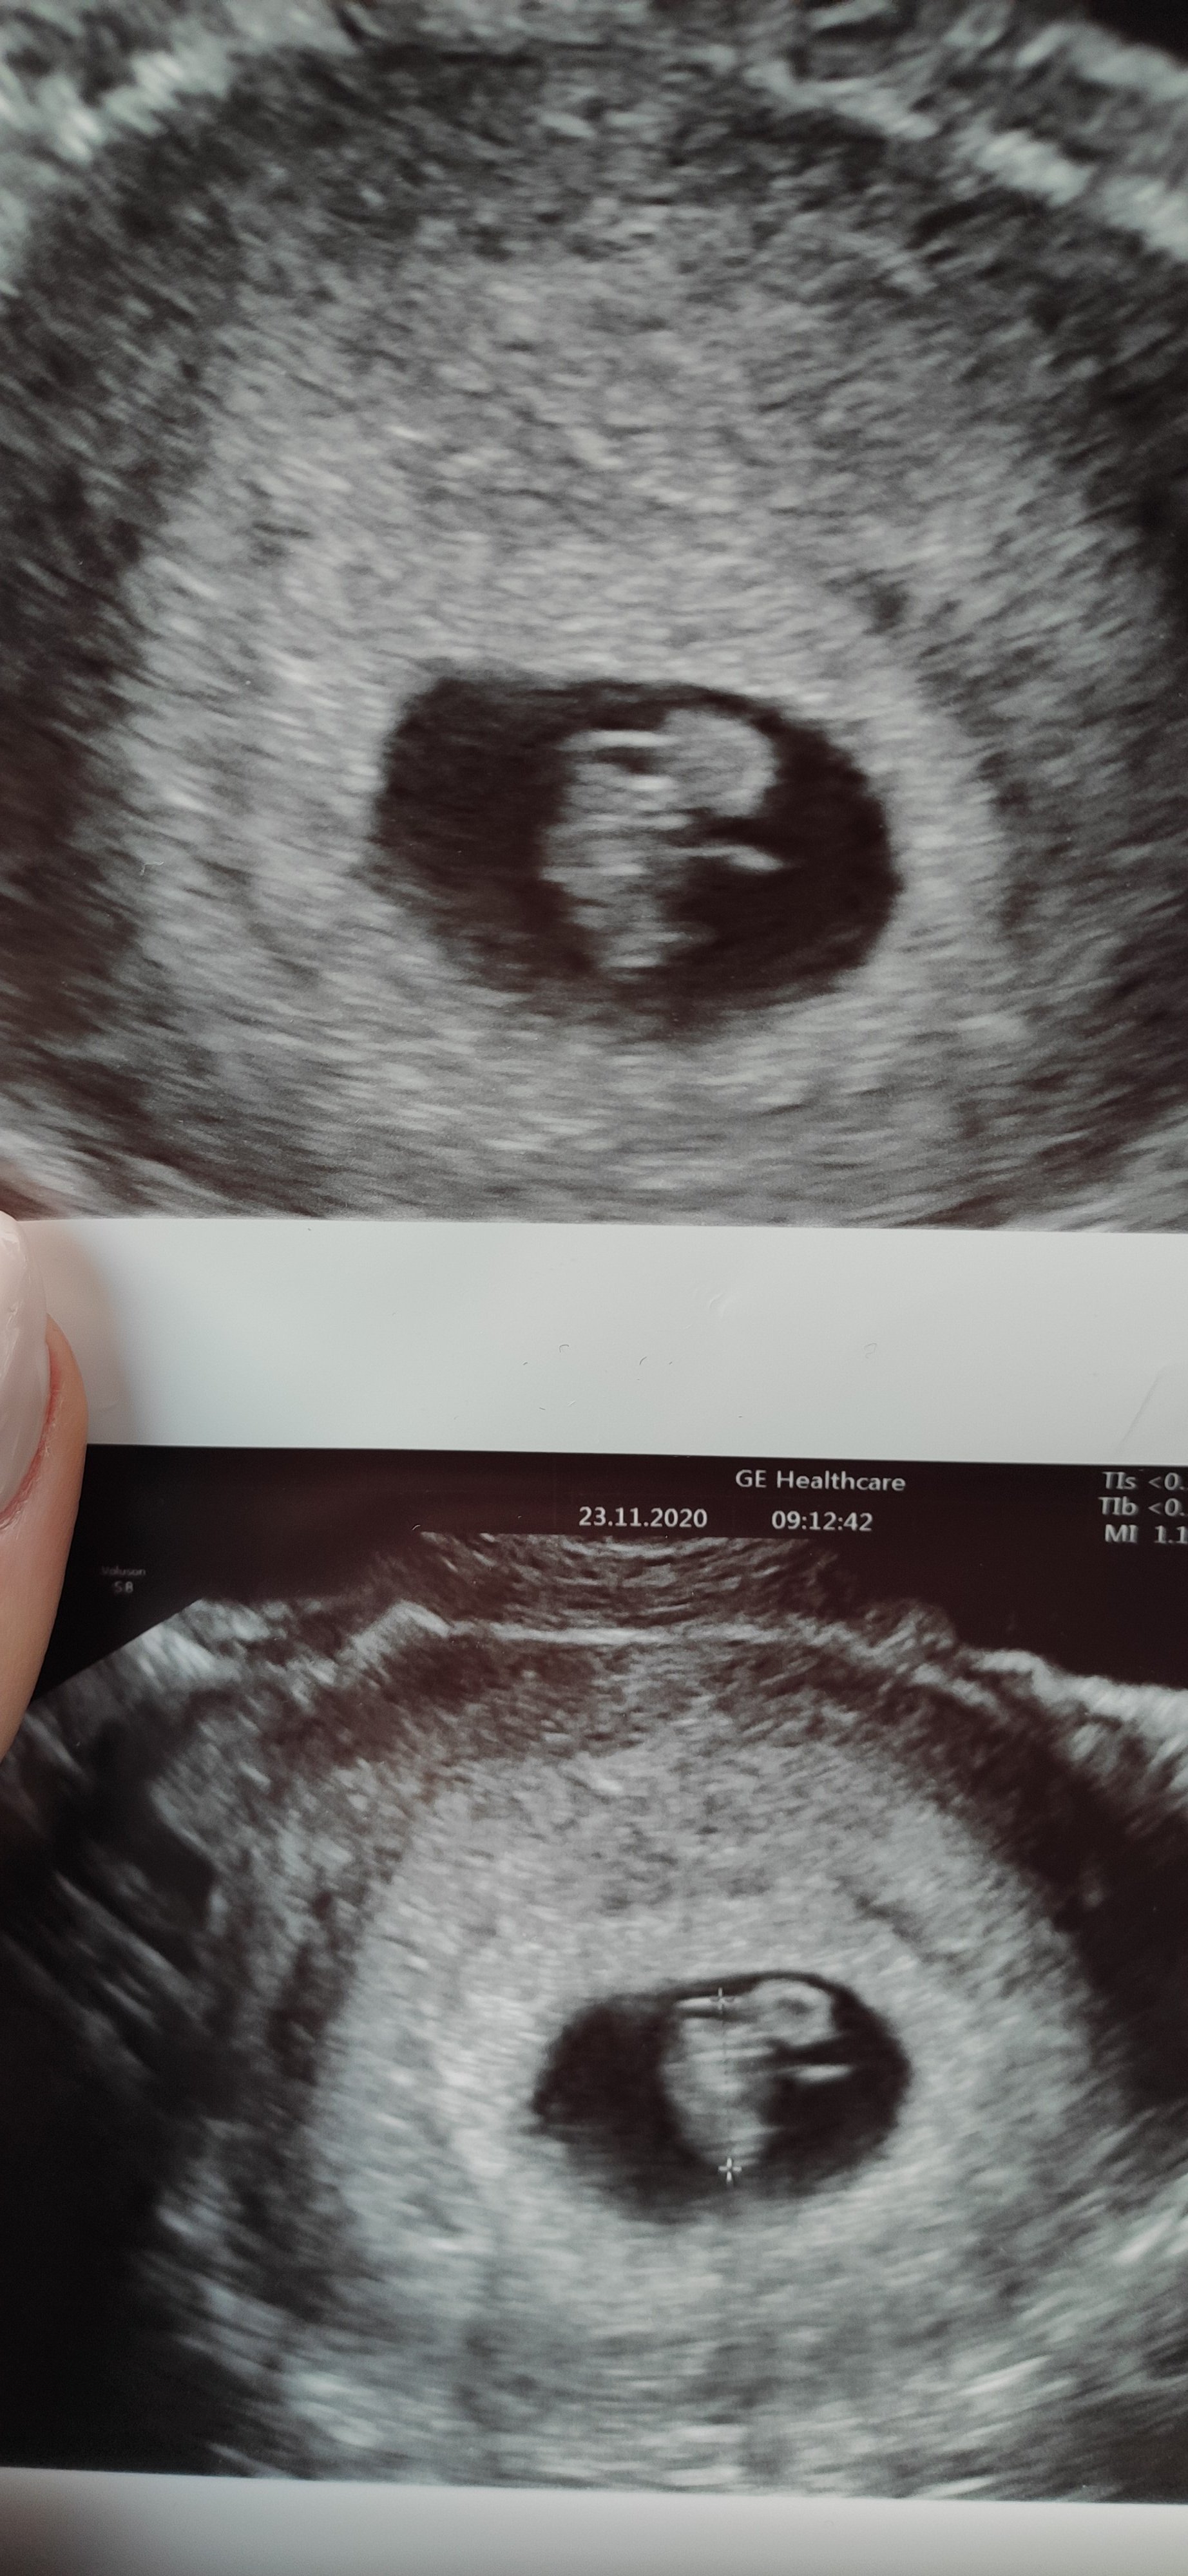

Ja dziś byłam na wizycie i serduszko pięknie bije